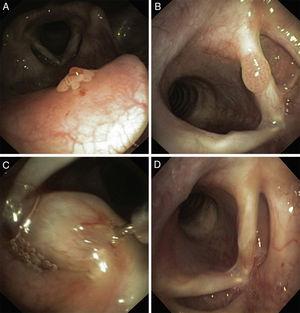

One patient had an epiglottis and vocal cord involvement and 3 patients had more extensive lesions: larynx and trachea in one case, pharynx, larynx and trachea in another case and one with a more exuberant and extensive form involving nasal cavity, pharynx, larynx, trachea and bronchus (Figure 1, Figure 2, Figures 3 and 4, Figure 5, Figure 6, Figure 7).

Figure 1. Papiloma of the right nasal fossa (A), pharynx (B), larynx (C) and right B1 bronchus (D).

| Location of papillomas | Nasal fossa, left conjunctival sac, larynx and bronchus ( Fig. 1 ) | Larynx, trachea | Larynx: vocal cords, epiglottis | Larynx, trachea |

RPP is more common in the larynx, particularly in the vocal folds and rarely involves the trachea or bronchus. In our series the larynx was the most affected by RPP especially the glottic area but trachea was also frequently involved. We also had a patient with involvement of the entire respiratory tract: from nasal fossa to bronchus.